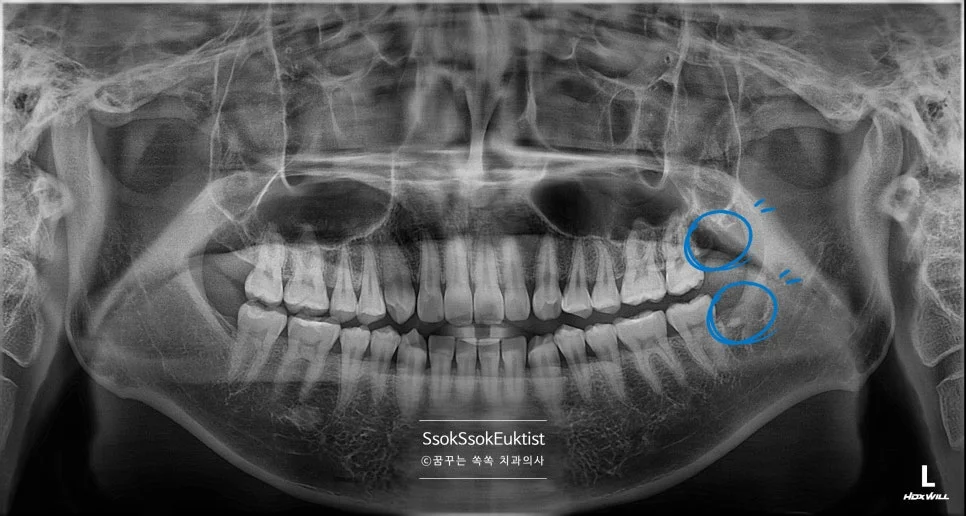

중간 난이도 완전 매복 사랑니 파노라마 엑스레이

잇몸 하방에 완전히 묻혀 있는 완전 매복 사랑니입니다. 사랑니가 맹출 하면서 잇몸의 통증을 호소하는데요, 뒤의 턱뼈와의 공간이 부족하여 어차피 매복될 치아라 바로 발치를 말씀드립니다.

깊숙이 매복되어 있어 잇몸 절개를 하고, 치아 상방의 치조골을 일부 삭제를 하고, 잘 나올 수 있게끔 사랑니 머리를 분리한 후 발치를 시행합니다.

CBCT 3차원 영상 — 사랑니와 신경관의 인접 관계 확인

발치 전 CT를 보면 신경관과 맞닿아 있어 발치 난도가 높은 케이스임을 알 수 있습니다.